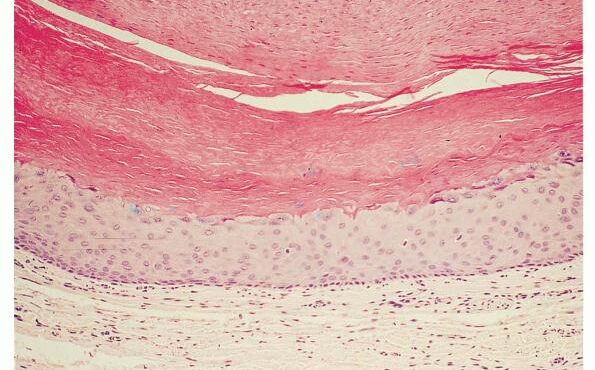

Eosinophilic fasciitis = التهاب الصفاق بالحمضات Eosinophilic Fasciitis Shulman’s Syndrome First described in 1974 , eosinophilic fasciitis is a scleroderma-like disorder characterized by inflammation and thickening of the deep fascia. It has a rapid onset associated with pain, swelling, and progressive induration of the skin leading to exaggerated deep grooving of the skin around superficial […]